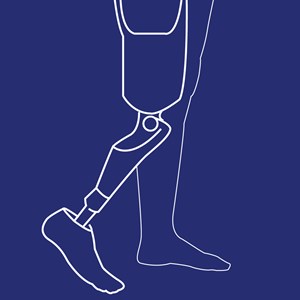

Underbensprotese (TT protese)

Type: pdf

Størrelse: 769 KB